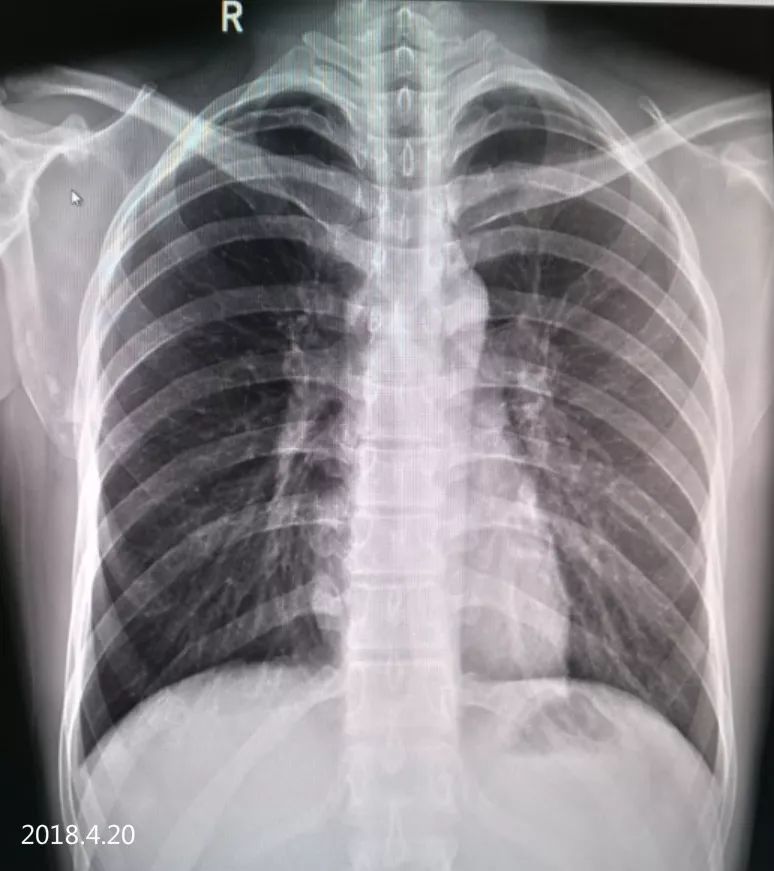

2018.4.20 经过约20天的治疗,肺组织已复张